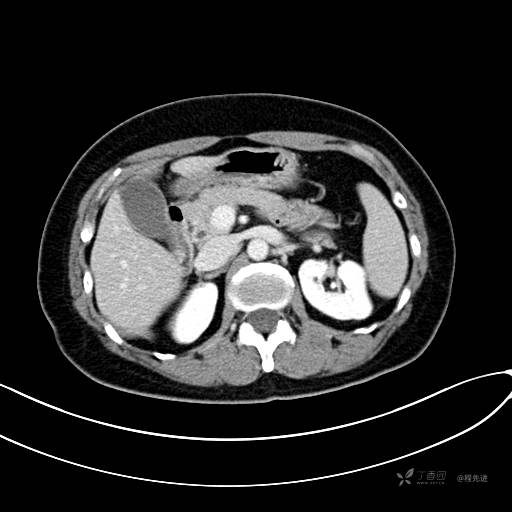

CT增强静脉期